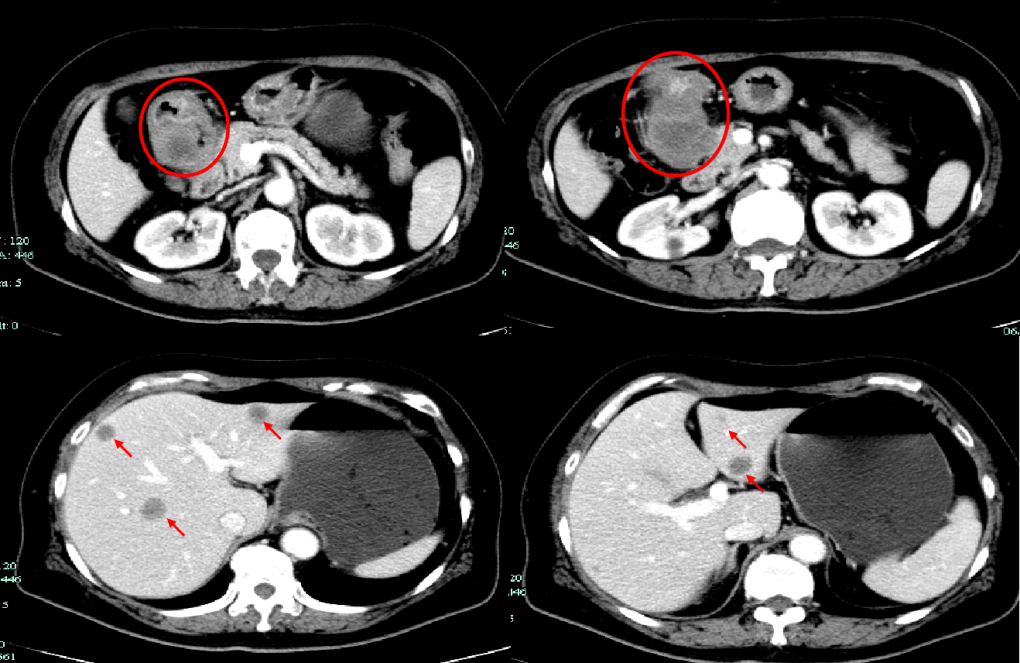

CT-T

CT-H1

影像学检查结果评估:cPD。